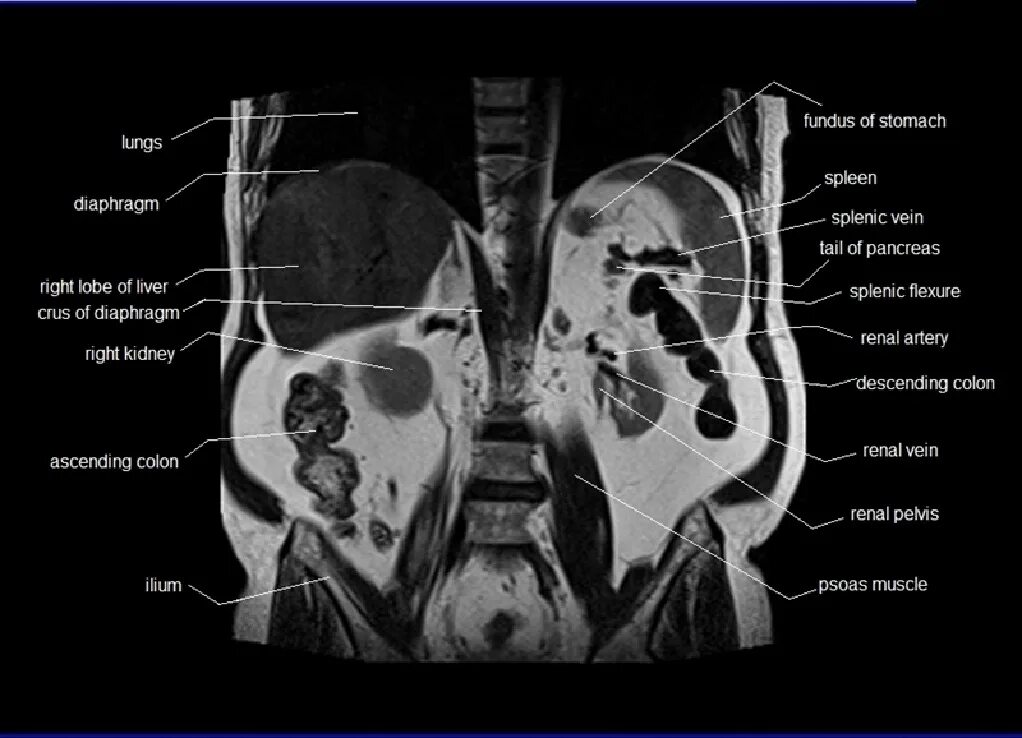

Что входит в мрт забрюшинного пространства